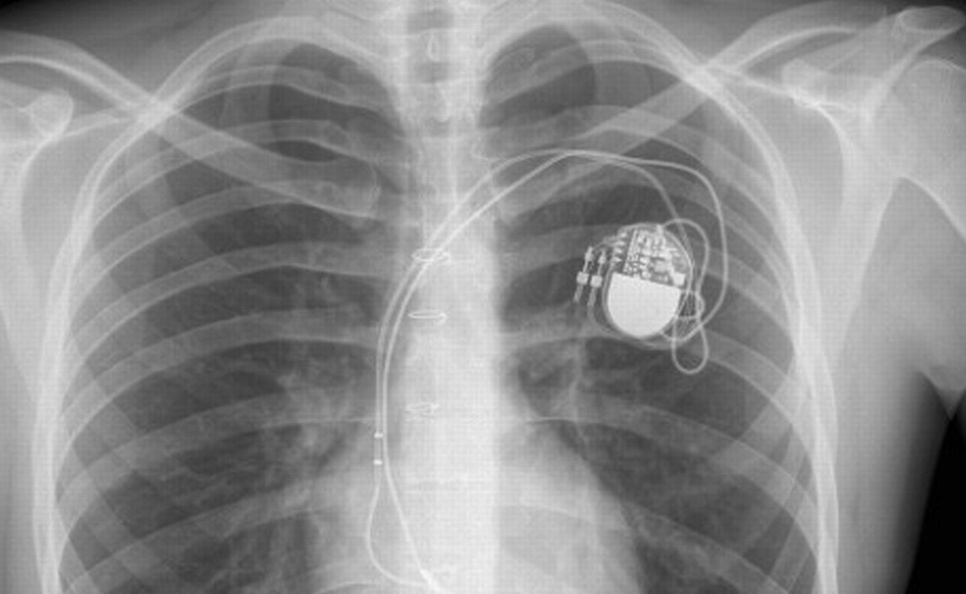

Donc, pour résumer, la FDA (Food and Drog Administration) a lancé une joyeuse alerte en affirmant de “potentiels problèmes de sécurité avec certains pacemakers“. Evidemment, tout le monde a commencé à paniquer et, Facebook aidant, l’information est vite partie en sucette sans que personne ne s’aperçoive du fond du problème.

Pour en revenir à la source de cet appel à la vigilance de nos amis américains en manque de Barack (Fraiture… Comprenne qui pourra, et surtout pas nos amis français), la FDA a simplement détecté que le moniteur de la marque Merlin était potentiellement “hackable”. Il s’agit du transmetteur Merlin@home conçu par l’entreprise St. Jude Medical qui envoie les informations du patient dans le Cloud. Ces données peuvent être consultées par le brave médecin qui pourra ensuite adapter le rythme du pacemaker.

Vous l’aurez compris, si cette chaine venait à être piratée, les informations se trouvant sur le Cloud ne pourraient donc pas refléter les données réelles et le médecin pourrait donc adapter la configuration du pacemaker de façon tout à fait erronée.

En conclusion, pas de panique, le fabricant a déjà mis en place un correctif qui ferme toutes les portes à de belliqueuses personnes qui passent leur temps à pirater ce genre de dispositif, c’est bien connu. Si vous avez un parent qui en possède un, allez donc le rassurer : tout va bien ! Si vous êtes la compagne d’un coeur faiblard, allez donc faire un tour chez Hunkemoller, les soldes sont toujours d’actualité.